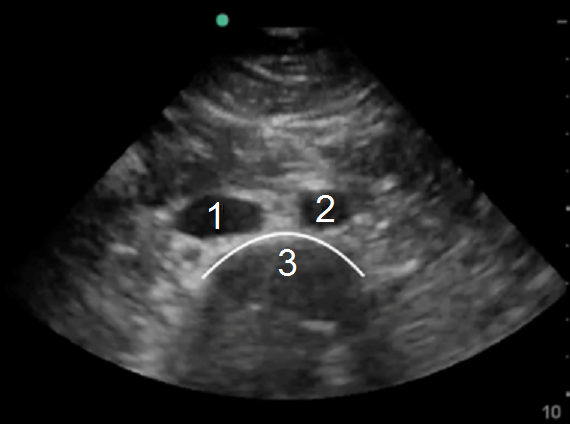

RUSH 腹部主动脉图像

下腔静脉 (IVC)

主动脉 (Ao)

脊柱阴影